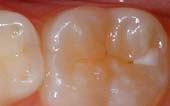

A sealant is a protective coating that is applied to the chewing surfaces (grooves) of the back teeth (premolars and molars), where four out of five cavities in children are found. This sealant acts as a barrier to food, plaque and acid, thus protecting the decay-prone areas of the teeth.

Before Sealant Applied

After Sealant Applied